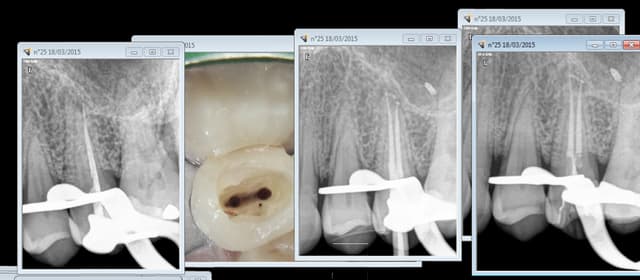

Ne cherche pas à te justifier Chicot, tu avais raison, tu ne pouvais pas la laisser comme ça ta bretonne qui bruxe, ses dents étaient suffisamment délabrées, je ne vois pas ce qu'un CDC trouverait à redire, il ne manquerait plus que ça!

Je suis d'accord. Un compo ne serait pas une méthode d'obturation pérenne, donc couronne indiquée.

Tant mieux pour toi si les DC de ta région sont cool. Par ici la réponse qui tombent régulièrement sur ce genre de cas c'est : "on ne traite pas le bruxisme, et l'usure qui en découle avec dévitalisation, inlay-core, et couronnes"